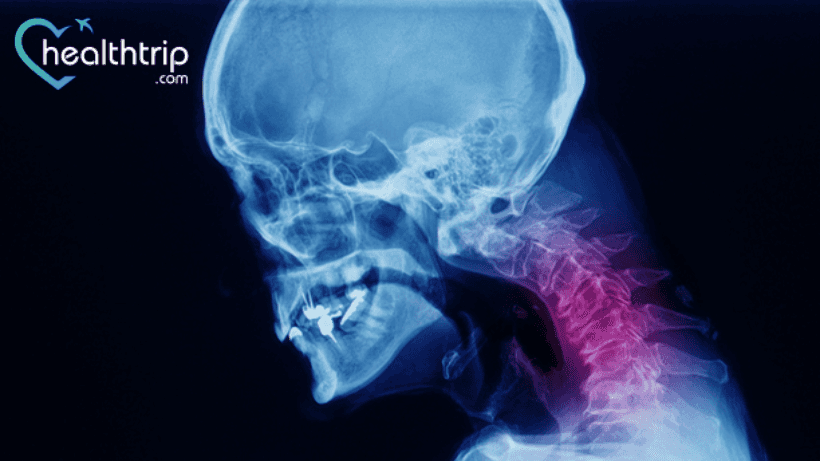

ሁሉም ሌላቀዶ ጥገና ወይም ሂደት ብዙ አደጋዎችን እና ውስብስቦችን ያመጣል. ነገር ግን፣ ለአንዳንድ የቀዶ ጥገናዎች አደጋው ዝቅተኛ ቢሆንም፣ በደቂቃ ውስጥ ከባድ ችግሮች የመፍጠር እድሎችን ችላ ማለት የለብዎትም።. እዚህ ላይ የፊተኛው የማኅጸን አንገት ዲስካቶሚ እና የመዋሃድ ቀዶ ጥገና ችግሮችን ተወያይተናል. ተመሳሳይ ነገር ለመማር ማንበብዎን ይቀጥሉ.

የፊተኛው የማኅጸን አንገት ዲስክቶሚ እና ውህደት አብዛኛውን ጊዜ የማኅጸን ስፖንዶሎሲስ ወይም የዲስክ እርግማን ማይሎፓቲ/ራዲኩላፓቲ ላለባቸው ታካሚዎች ይመከራል።

ለወግ አጥባቂ ህክምና ምላሽ የማይሰጥ. በተጨማሪም፣ አለመረጋጋት በሚያስከትሉ አንዳንድ አደገኛ፣አሰቃቂ ወይም ተላላፊ የሰርቪካል አከርካሪ ሂደቶች ላይ ሊታወቅ ይችላል።.